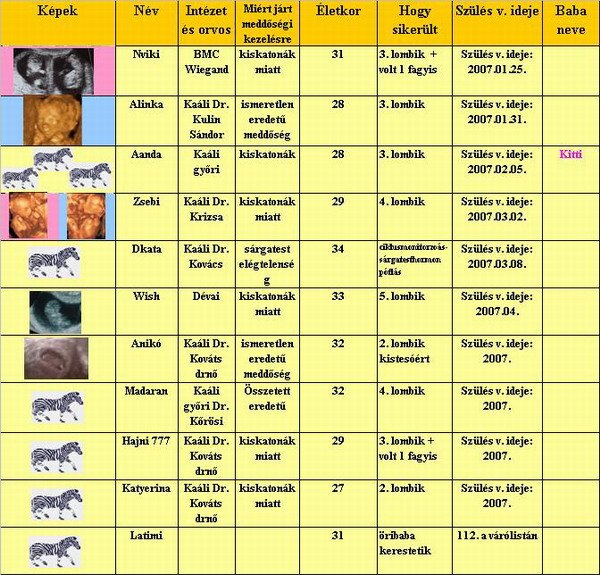

A profilba ha bemész akkor ott van egy nagy fehér rész előtte hogy aláírás oda kell bemásolni.

Viki!

Nagyon aranyosak a képek. Lenne egy kérdésem. Betegyem a táblába az új képeket, csak mit csináljak a szégyenlős kislánnyal? Vagy maradjon ami volt?

Anikó!

Hát nem hangzik valami jól ez az egész. És akkor valami újabb ötlet?

Lányok!

Megosztom veletek a nap örömét. Mi is voltunk 4D-s uh-n és hát felejthetetlen élmény volt. Tündériek voltak annyit mozogtak. A kisfiúnk a köldökzsinorral játszott, a kislányunk meg védte az arcát és ette a kezét. A kisfiú pont a kislány arcát rugdossa.

Lassan a neveket is közkincsé tesszük, de még nem 100%-ék,így várunk egy kicsit.

Ime a kisfiúnk:

Ime a kislányunk:

[/url

[/url